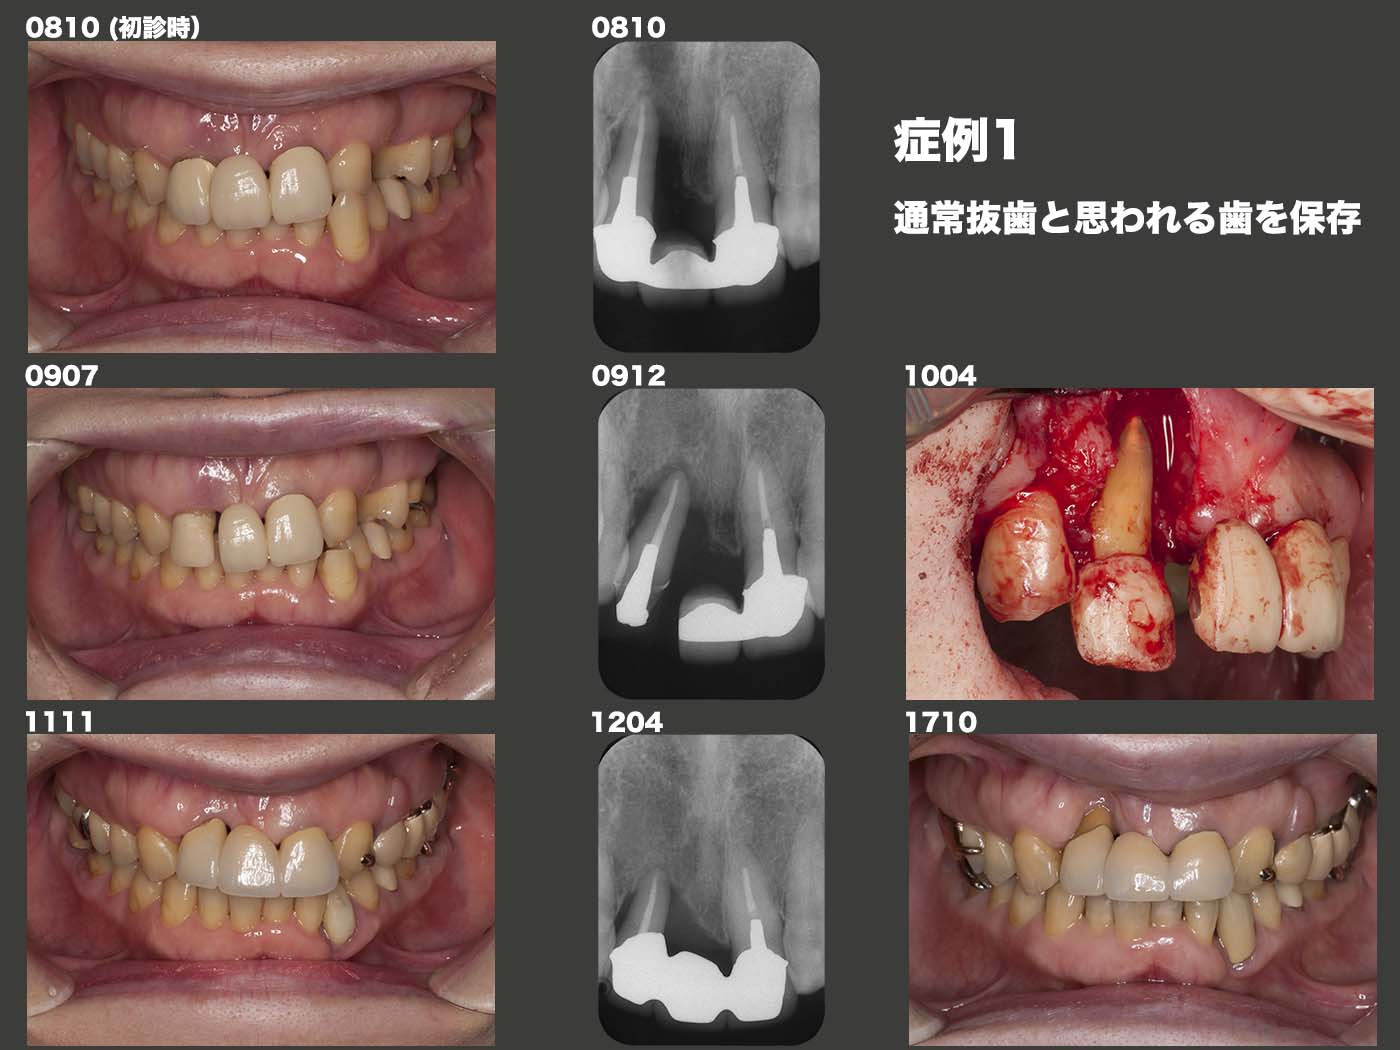

症例1 通常抜歯と思われる歯を保存

2008年10月再初診、65歳女性。親の介護が終わり、本格的な治療を行いたいとのことであった。全体的に歯周病が進行していたが、ここでは右上2について述べ る。歯周ポケットは12mmあり、抜歯の可能性が非常に高かったが、本人の希望もあり、保存する方向で治療を進めた。2009年3月に、右上2の冠を除去し、下の歯と当たらないように細工し、この状態で暫く経過を観察した(専門的には自然的挺出)。なおこの間は、他の歯の治療を行っていた。2010年4月の時点で歯周ポケットはまだ10mm存在した。ここで外科的治療を行ったが、スライドに示すように、遠心側(右上3側)以外の歯槽骨はほとんど消失していた。しかし、同年10月の時点で歯周ポケットは5mmに減少した。もう1年経過を観察し、2011年11月、メタルボンドブリッジを装着した。2017年10月、歯肉は退縮してしまったが、歯周ポケットは3mm以下であり、問題なく経過している。